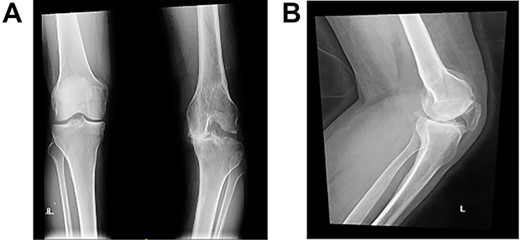

Long weight-bearing knee radiographs showed severe osteoarthritic changes, 18° knee genuvarum and extension deformity of the left distal femur (Fig. 2). Skyline view showed severe arthritic changes (Fig. 3).

Preoperative plain radiographs; (A) severe osteoarthritic changes affecting the left knee with narrowing of the medial knee joint compartment; (B) left femur with dorsal angulation above the condyles and severe patella baja.